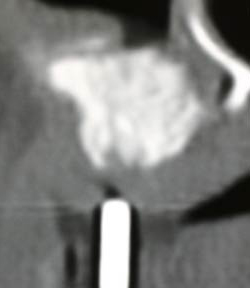

3) 上顎臼歯部での歯槽骨欠如

上顎臼歯部では上顎洞があり、歯槽骨の高さがなく、インプラントを植える事が困難な場合があります。しかし上顎洞の底部に骨を移植して、十分な骨を作ることが可能です。下の写真の術前のCTでは非常に薄い骨があるのみで、到底人工歯根は植えられません。しかし上顎洞下部に骨移植を行い、十分な骨を造成する事ができます。骨が足りない場合は人工骨(β-TCP)を自家骨に混ぜて、増量します。

術後CTで白くなっているのが、新しく出来た骨です。